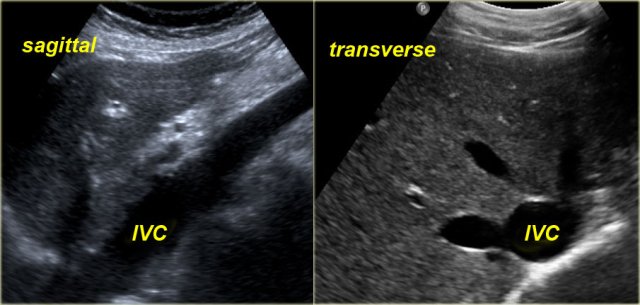

Sonographic signs of RV failure:

- Dilatation of the inferior vena cava (IVC) and hepatic veins

- Hepatomegaly

- Ascites

The indication for ultrasound examination in many of these patients is abnormal liver function tests.

It is therefore important to consider the possibility of RV failure when a patient presents with liver enzyme abnormalities.

Under normal conditions dynamic ultrasound will demonstrate changes in caliber of the IVC.

These changes in caliber can be attributed to variations in blood flow in the IVC in accordance with the respiratory and cardiac cycles.